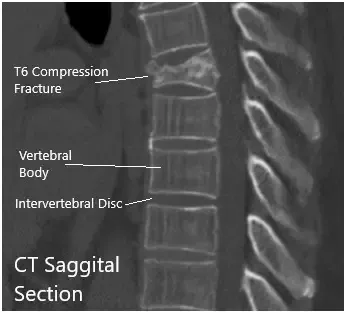

TAC Sagital y Cesárea coronal.

La TC reveló fractura aguda moderada por compresión de cuña asociada al cuerpo vertebral T6. La corteza posterior del cuerpo vertebral T6 se imprime ligeramente sobre el margen anterior del saco dural torácico. El hematoma mínimo se sitúa entre el cuerpo vertebral T6 y la pleura circundante.

Había una configuración normal de los cuerpos vertebrales torácicos restantes. Los espacios del disco torácico no están estrechados. No se demuestran protrufacciones discales posteriores ni hernias. El estrechamiento no está asociado con los forámenes neurales torácicos.